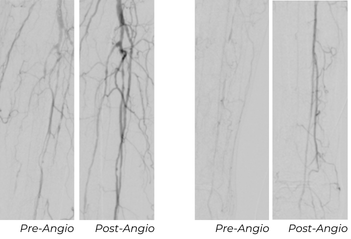

Follow-Up Outcomes

At his 30-day follow-up appointment, the wound was significantly smaller with healthy tissue formation, measuring 0.8x0.3 cm, down from the original wound size of 1x0.5 cm. At the 90-day follow-up appointment, his ABI was normalized at 0.93 and his toe pressure improved to 33 mmHg.

Key Takeaway

This case highlights progressive vessel remodeling after Serration Remodeling Therapy, continued luminal improvement, normalization of perfusion metrics, and complete wound healing within 90 days.

This patient needed a toe amputation one month after his procedure due to osteomyelitis. After one-month, the patient had wound dehiscence, therefore a repeat angiogram was performed. Repeat imaging showed excellent remodeling, no restenosis, and a strong, in-line flow. The wound has progressed significantly, and the patient is near healed.

Despite this patient’s advanced age and wound complications, the TPT vessel demonstrated durable patency and positive remodeling after Serranator use, with no need for repeat angioplasty.